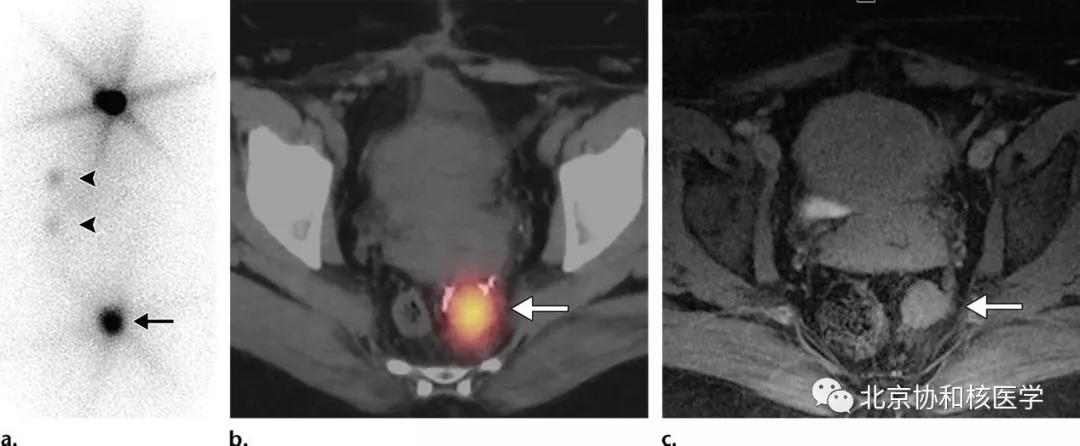

39岁女性,恶性卵巢甲状腺肿病史,行右侧卵巢切除术、甲状腺切除术、碘131治疗,碘扫可见残余甲状腺摄取、盆腔转移灶摄取及肝转移灶摄取: